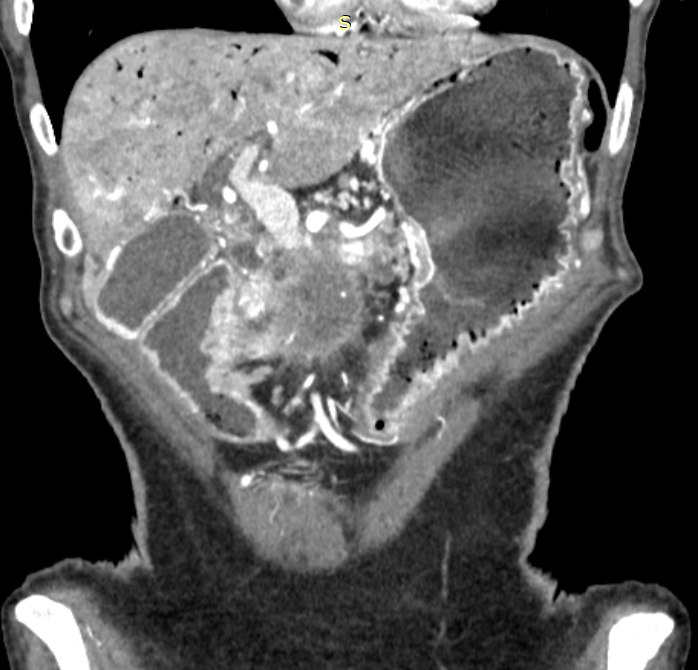

Пациентка 71 года с недавно установленным диагнозом опухоли поджелудочной железы обратилась в отделение экстренной помощи.

Очевидная дуоденальная кишечная непроходимость, обусловленная опухолевым ростом поджелудочной железы.

Помимо ожидаемой картины непроходимости были выявлены редкие и клинически значимые изменения:

газ в системе воротной вены (портальный пневматоз);

интрамуральный газ в стенке желудка;

тромбоз верхней брыжеечной вены;

локальный тромбоз верхней брыжеечной артерии.

некроз желудка на фоне тромбоза верхней брыжеечной артерии;

воздушная эмболия из поверхностных вен пищевода и желудка при синдроме Мэллори–Вейса.